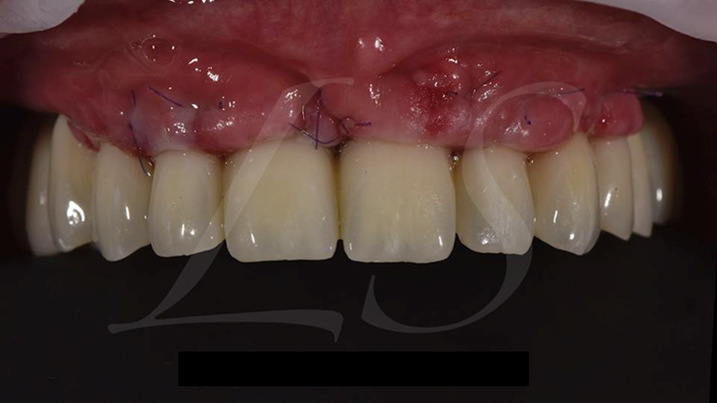

Clinical case: Full-arch implant treatment with immediate loading & extraction implantation

- Courtesy of Dr. Laurent Sers, France -

AnyRidge, R2GATE, guided surgery, Dr. Laurent Sers, immediate loading, maxilla

AnyRidge implant system, R2GATE, Digital prosthesis

“Patient’s smile was recovered on the day of surgery

with reliable & highly-aesthetic results using AnyRidge & R2GATE. ”